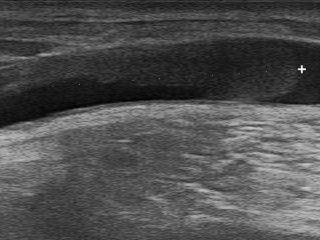

L’échographie utilise la propagation des ultrasons pour créer les images. Cette technique non-irradiante permet de réaliser les examens en temps réel. L’utilisation de différentes sondes échographiques ayant un niveau de résolution plus ou moins important permet de remédier à toutes les situations, aussi bien chez les petits chats que chez les grands chiens.

L’échographie abdominale permet la détection et le diagnostic de la majorité des pathologies abdominales. D’autres régions comme le cou, le thorax ou les tendons peuvent également être examinées échographiquement.

Certaines pathologies chirurgicales comme les obstructions gastro-intestinales dues à l'ingestion d'un corps étranger, les torsions spléniques, ou les calculs urinaires peuvent facilement être diagnostiquées à l'échographie.